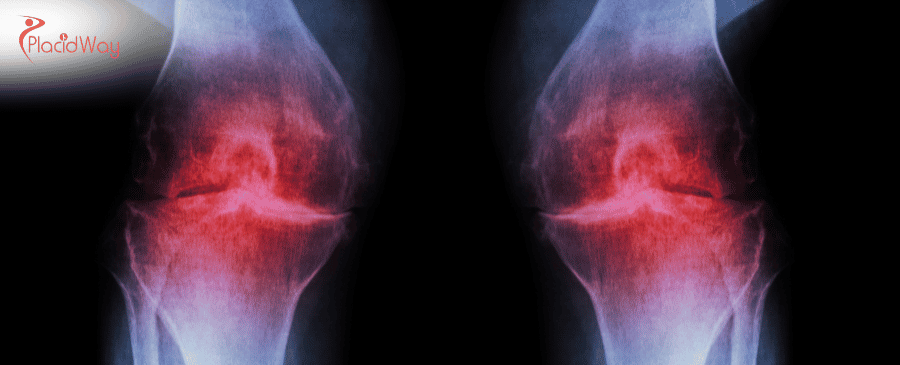

For millions in the UK, osteoarthritis (OA) is a daily battle with chronic joint pain, stiffness, and reduced mobility. While traditional treatments like physiotherapy, pain medication, and eventual joint replacement surgery offer relief, many are now seeking innovative solutions that address the root cause of cartilage degeneration. Stem cell therapy has emerged at the forefront of regenerative medicine, offering a promising, minimally invasive alternative to slow disease progression and potentially regenerate damaged tissue.

Stem cell therapy for osteoarthritis is a non-surgical procedure that leverages the body's natural healing mechanisms. It aims to reduce inflammation, alleviate pain, and potentially stimulate the repair of damaged cartilage within the joint by introducing a concentrated dose of powerful regenerative cells.